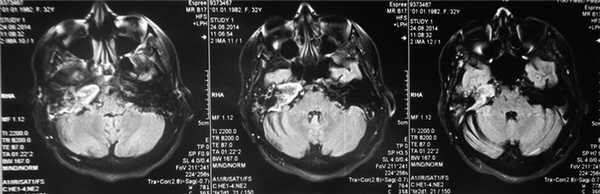

По результатам МРТ головного мозга правая пирамида височной кости деформирована, увеличена в объеме, выполнена субстратом размером до 5,5—2,8—3 см, распространяющимся на область внутреннего слухового прохода, заднего полукружного канала, медиальные отделы барабанной полости, сосцевидный отросток. Описанный субстрат изо-гипоинтенсивен в режиме Т1, гиперинтенсивен — в Т2 и non-EPI DWI (рис. 2). Заключение: признаки рецидива холестеатомы с деструктивными изменениями структур внутреннего и среднего уха на фоне хронических воспалительных изменений.

Рис. 2. Магнитно-резонансная томография головного мозга пациентки М. Деформированная, увеличенная в объеме пирамида височной кости выполнена мягкотканым субстратом.